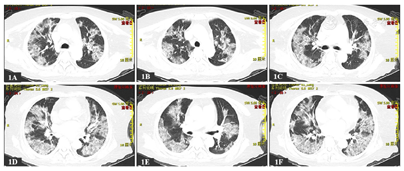

入院前辅助检查(2023年1月8日):全血细胞分析:红细胞计数4.27×1012/L,白细胞计数10.2×109/L,淋巴细胞计数0.86×109/L,中性粒细胞计数8.80×109/L,淋巴细胞百分比8.5%,中性粒细胞占比0.861,血小板计数363×109/L,余正常。肾功+电解质+肝功+心肌酶学+血脂全套:白蛋白30.0 g/L,白球比0.8,总胆红素24.3 μmol/L,门冬氨酸转移酶111.1 U/L,谷氨酰转肽酶115.0 U/L,尿素6.40 mmol/L,葡萄糖7.62 mmol/L,钾3.20 mmol/L,钙1.95 mmol/L,丙氨酸氨基转移酶46.8 U/L,胆碱酯酶2415.7 U/L,乳酸脱氢酶449.0 U/L,其余项目正常。凝血系统检查:纤维蛋白原6.74 g/L,凝血酶原比率1.18 g/L,D-二聚体6.45 mg/L,抗凝血酶Ⅲ 57.60%,凝血酶原活动度66.80%,纤维蛋白(原)降解产物21.35 μg/ml,余项正常。血清肌钙蛋白T 0.016 ng/ml,B型钠尿肽测定1920.0 pg/ml,C反应蛋白149.54 mg/L。新冠病毒核酸:阳性。新冠病毒抗原:阳性。肺部CT(图1):双肺病毒性肺炎;纵隔淋巴结肿大,部分钙化;主动脉、冠状动脉硬化。

经过治疗,患者发热、胸闷、气憋症状消失,咳嗽减轻,呼吸衰竭得到纠正(表4),新冠病毒被清除(表1),同时食欲改善,进食恢复,血象、血凝及生化指标逐渐恢复至正常水平(表2、表3、表5),各炎症标志物、N端钠尿肽基本降至正常水平,未继发真菌、细菌感染(表6)。1月29日复查肺CT显示肺部病灶面积较入院时吸收(图2A~2H),继续观察1周,于2月3日病情好转出院,叮嘱患者居家时继续氧疗,坚持俯卧位通气与呼吸操锻炼,口服利伐沙班抗凝(每次10 mg、1次/d),加强营养支持,患者肺功能明显改善,不吸氧状态下日常活动不受限,3月22日再次复查肺CT提示双肺病毒性肺炎吸收期改变,较1月29日范围缩小(图2I~2L);疾病顺利恢复,目前处于呼吸康复锻炼过程中。